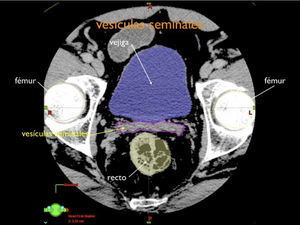

Otro avance médico fundamental es el desarrollo de consensos para la definición tridimensional de los volúmenes de tratamiento, a partir de las imágenes de tomografía axial computada, (TAC), tanto para los volúmenes blancos de tratamiento como para la definición de órganos a riesgo u órganos sanos que lo rodean (4,5) (Figuras 1-3).

Para mejor definición de los volúmenes blanco se incorpora la utilización de todos los tipos de imágenes tomográficas disponibles, TAC con y sin contraste, resonancia nuclear magnética, RNM, tomografía por emisión de positrones, PET CT con diferentes isotopos. Las imágenes de apoyo son fusionadas a la imagen de planificación para una óptima definición de los volúmenes (1).

Enfermedad de alto riesgo: la enfermedad de alto riesgo se caracteriza por la probabilidad elevada de tener compromiso tumoral extra prostático, traspasando la cápsula, invasión de vesículas seminales o metástasis a ganglios linfáticos (15).

En esta etapa la radioterapia externa tiene un rol importante al poder tratar todas las áreas con riesgo de alojar cáncer. Se debe tratar con IMRT o VMAT y el posicionamiento verificarse con IGRT. Se trata la próstata y vesículas seminales pudiendo o no incluir los ganglios pelvianos. En el último tiempo se ha estudiado la posibilidad de agregar braquiterapia de alta tasa como sobre impresión a la próstata, boost, para alcanzar una dosis más alta en la próstata (17). En esta etapa siempre se utiliza bloqueo androgénico concomitante aumentando la sensibilidad de la célula cancerosa a la radiación (18).